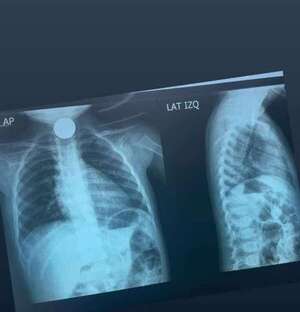

Un hallazgo tan inusual como inquietante se registró en el Instituto Nacional de Enfermedades Respiratorias y del Ambiente (INERAM), donde médicos detectaron y extrajeron un anillo de oro alojado en el pulmón de un paciente de 54 años. [Leer más]

El doctor Carlos Morínigo pilló la joya cuando el hombre fue para un control de rutina y, al hacerle una radiografía, saltó que tenía el "tesoro" en el bronquio. [Leer más]